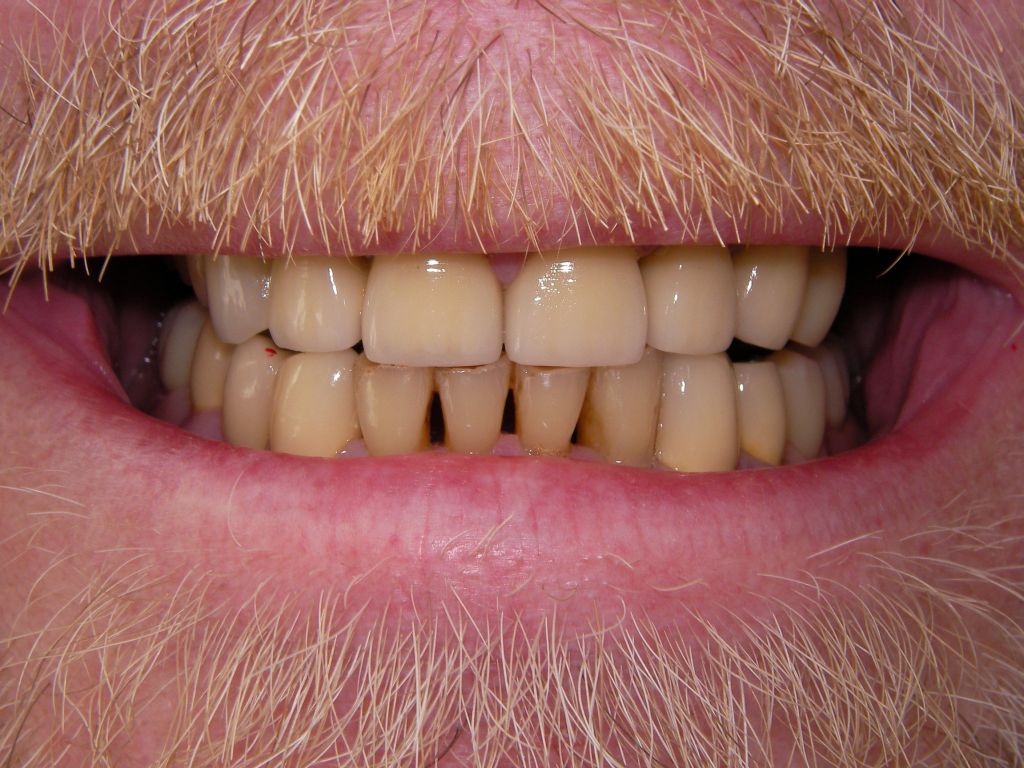

Hier das vorläufig letzte Bild dieses Falles mit maximaler Lippenöffnung einige Tage nach Eingliederung von Kronen und Prothesen bei der Nachkontrolle (Ende März 2006). Bislang lief, von einigen anfänglichen Prothesendruckstellen abgesehen, die aber leicht behoben werden konnten, alles glatt. Die Heiß-/Kaltempfindlichkeiten an den beschliffenen Zähnen, die häufig auftreten, waren nach der Zementierung der Kronen verschwunden. Die eigentliche prothetische Behandlung dauerte vom 22.2.06 bis zum 20.3.2006 (nur 5 Sitzungen), also 4 Wochen und war damit recht zügig. Ähnliche Fälle können auch 6 Wochen dauern.

Forciertes Lächeln